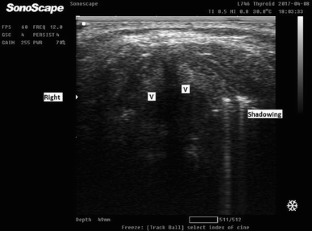

Fig. 4